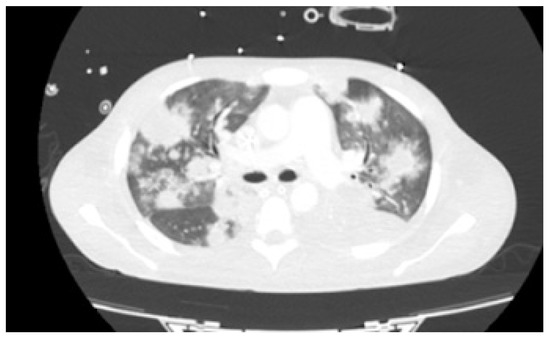

As fever, hypoxemia and raising of inflammatory parameters persisted without any additional agent identification, and after 41 days of empirical antibiotics, thoracic CT was repeated on day +43 (Figure 2). The exam demonstrated multiple homogeneous nodular lesions scattered throughout the parenchyma with increase in number and lesion volume. Even though broad-spectrum antibiotherapy was reintroduced that same day and ARV initiated with bictegravir/tenofovir alafenamide/emtricitabine (BIC/TAF/FTC) on day +46, dermatological, gastrointestinal, and respiratory signs and symptoms persisted. It is of note that mpox PCR on mucocutaneous lesion exudate remained positive on day +51. Due to progressive hypoxemia, bronchofibroscopy with bronchoalveolar lavage (BAL) collection was repeated on day +67. Besides positive mpox PCR on BAL, all other microbiological exams in this product were negative.

Figure 2. Thoracic CT scan on day +43 demonstrating multiple homogeneous nodular lesions scattered throughout the parenchyma.